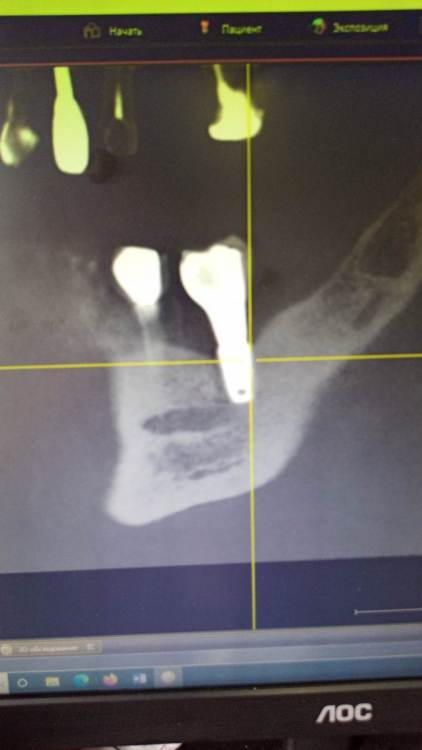

Зндрю Опубликовано 2 февраля, 2024 Автор Поделиться Опубликовано 2 февраля, 2024 (изменено) КТ имеется . Окончание импланта лежит на нижней ветви тройничного нерва, но не травмирует его. Со слов независимого имплантолога, у которого был на консультации, иначе симптомы были бы неврологические , а их нет . Изменено 2 февраля, 2024 пользователем Зндрю Ссылка на комментарий

kramer Опубликовано 7 февраля, 2024 Поделиться Опубликовано 7 февраля, 2024 В принципе понятно. Лично мое мнение, что надо удалять оба имплантата (ближний выглядит недозаглубоенным (плохо видно), дальний слишком близко к нерву, что скорее всего и дает симптомы. Установить новые импланты, сделать мостовидную конструкцию. Ссылка на комментарий

Зндрю Опубликовано 7 февраля, 2024 Автор Поделиться Опубликовано 7 февраля, 2024 (изменено) 3 часа назад, kramer сказал: В принципе понятно. Лично мое мнение, что надо удалять оба имплантата (ближний выглядит недозаглубоенным (плохо видно), дальний слишком близко к нерву, что скорее всего и дает симптомы. Установить новые импланты, сделать мостовидную конструкцию. На месте дальнего годом раньше стоял аналогичный имплант, но он был расположен выше. Период интеграции с костью сроком в 4 месяца он пережил успешно, а вот после установки формирователя десны началось воспаление, сопровождаемое обильной грануляцией десны, которое закончилось периимплантитом и удалением данного импланта . Через полгода на это же место был установлен нынешний имплант, но уже с максимальным погружением в кость. При его установке врач попал мне им в тройниный нерв, это было ясно потому как меня словно током ударило. Он тут же открутил его немного обратно и спросил меня, чувствую ли я боль, на что я ответил что нет . Он так и оставил, и дальнейший период интеграции с костью проходил без осложнений. Установка формирователя десны тоже осложнений не вызвала , боли начались только после установки коронки. Самое главное - что первый винт стоял на достаточном расстоянии от нижней ветви тройничного нерва, но болевые ощущения была абсолютно идентичны что и со вторым винтом - а именно появлялись исключительно через несколько часов после вкручивания коронки, при этом я даже еще ни разу не успевал ничего жевать . Изменено 7 февраля, 2024 пользователем Зндрю Ссылка на комментарий